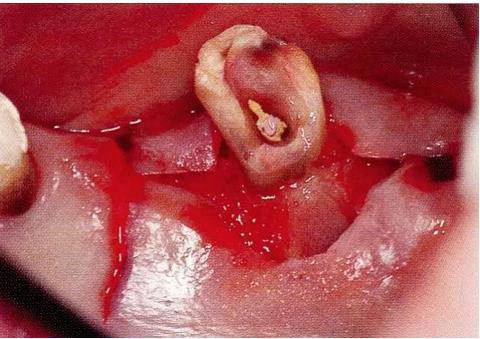

▼圖16-4

圖16-4進(jìn)行牙齒分割時(shí),如圖所示一樣,要確保分割去除的牙根邊緣不會(huì)殘留在牙槽中間骨脊。如果有邊緣殘留,會(huì)造成軟組織發(fā)紅,引發(fā)炎癥。

▼圖17

圖17 將右上6近中頰側(cè)根拔除,考慮到修復(fù)物清潔性的情況下進(jìn)行備牙。牙齒分割后如果有邊緣殘留,就會(huì)使切割面的牙齦發(fā)紅無(wú)法治愈。